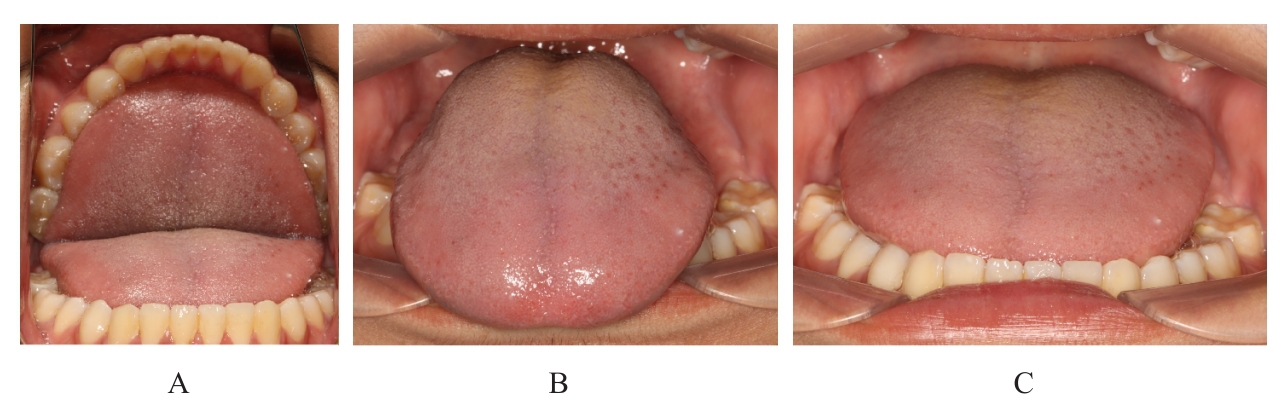

Grade Ⅲ open bite complicated with tongue hypertrophy treated by mandibular incisor extraction:A case report and literature review

Lei TIAN,Yuyan LIU,Yuqing WANG,Zhiyu ZHANG,Xiumei SUN( )

- Department of Orthodontics,Stomatology Hospital,Jilin University,Changchun 130021,China